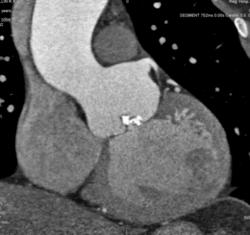

Мужчина 35 лет с клиникой стеноза аортального клапана. На КТ выявлен двустворчатый клапан с обызвествлениями в створках. Луковица аорты и восходящий отдел значительно расширены. Отмечается также вариант отхождения левой коронарной артерии - левая передняя нисходящая и огибающая отходят непосредственно от аорты. Правая коронарная артерия гипопластична.